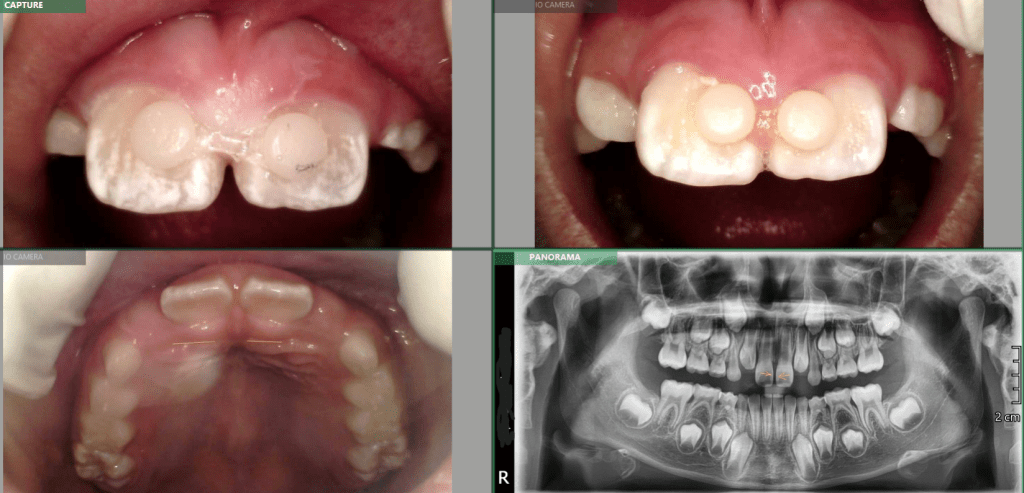

Mackenzie. L – Myobrace – Age 9

Adaptive Orthodontics TREATMENT STARTED AT AGE : 9 Myobrace K1 MediumMixed DentitionClass 2 Div IModerate 1st Review – 2023-03-01 YELLOW = Initial 2022-10-29 BLUE = 1st Review 2023-03-01 Compliance was not good in the first quarter. Not much expansion seen on buccal side 2nd Review – 2023-05-30 YELLOW = Initial 2022-10-29 BLUE = 2nd Review2023-05-30… Read.